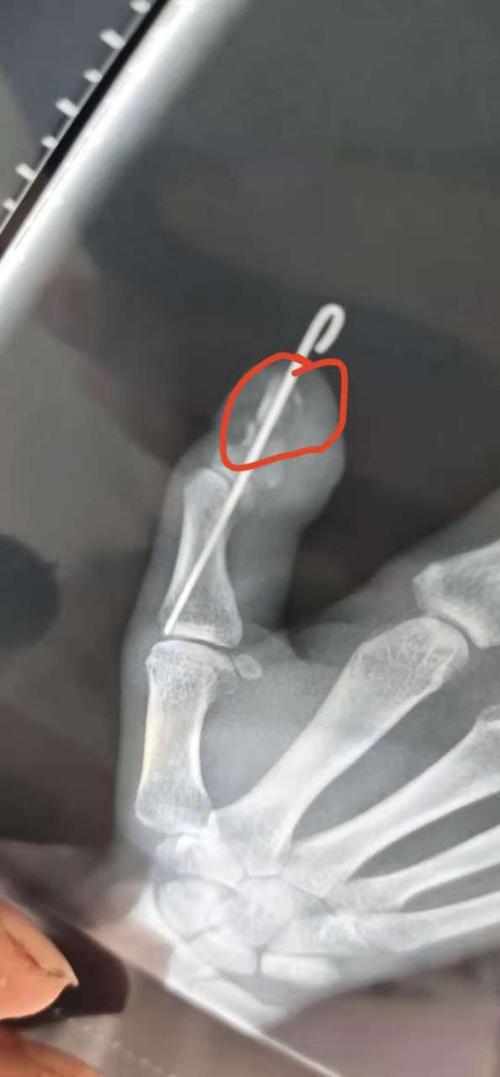

新疆一特警手指打钢针照片引发全国网友关注

梁平邹总:拇指骨里打钢针

前段时间指头受伤,钉了两根钢针,一根2300,什么材质这么贵?

骨折打钢针图片

骨头打钢针图片

手指打钢针图片

骨折钢针图片

骨折手术钢针图片